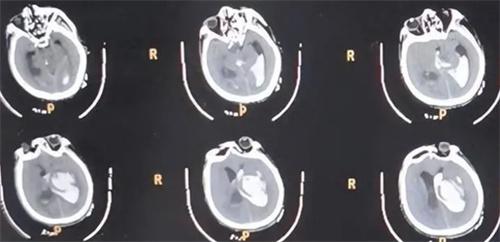

近日,在黑龍江肇東市發生了一起男子暈倒后遭遇家豬啃食的事件。據了解,這位66歲的老人身患高血壓和糖尿病多種慢性疾病,當天在喂養家豬的時候,突發疾病導致暈倒在豬圈內。由于事發突然老人并沒有被及時發現得到救治,反而是被自家養的家豬啃食下體,現場情況十分的慘烈。被人們發現的時候,患者的生殖器官已經被家豬啃食一空,還由于大量的出血導致昏迷,整個人的病情十分危重。

老人送醫之后,多個學科的醫生得知此事迅速展開了緊急搶救工作,經過一系列的全面診斷和檢查。醫生們最終發現,患者是存在比較嚴重的多臟器衰竭和感染,病情也顯得十分的緊要,后續經過緊張和有效的治療之后,患者終于是脫離了生命危險。